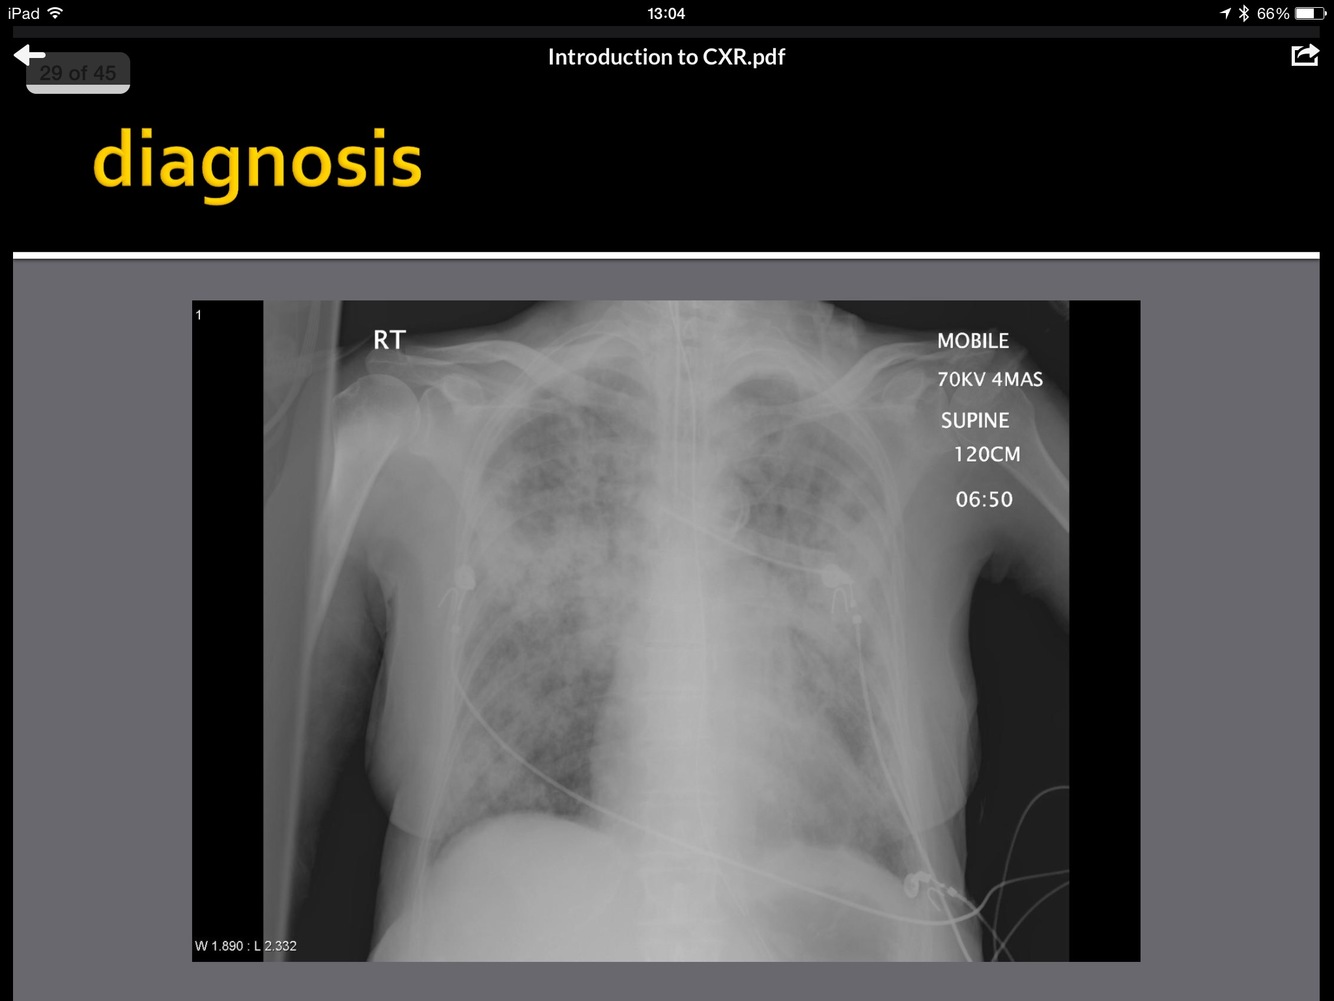

what does this image show?

Dilated Colon - Sigmoid Volvulus

This occurs in cases of long-standing chronic constipation where patients develop a large, elongated, relatively atonic colon, particularly in the sigmoid segment. It is often referred to as acquired or idiopathic megacolon. In sigmoid volvulus, a large sigmoid loop full of faeces and distended with gas twists on its mesenteric pedicle to create a closed-loop obstruction. If uncorrected, venous infarction leads to perforation and faecal peritonitis.